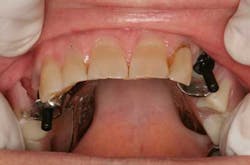

After uncovering the implants, Locator abutments were torqued to 30 Ncm (figure 1). Parallel posts were seated on the abutments, and complete seating of the original RPD was confirmed (figure 2). It was planned to remove the existing metal clasps at sites of Nos. 5 and 11, so they were removed at this time to prevent interference with the parallel posts. Clasps can also be removed at the lab if desired. A small amount of PVS adhesive was placed on the intaglio surface prior to seating the RPD.